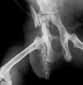

| Vom

Wellensittich bis zum Bernhardiner - vom Zahn bis zur Hüfte

können und müssen scharfe

und kontrastreiche

"Standbilder" angefertigt werden. |

| Zugelassene

Röntgenstelle für HD

(Hüftgelenksdysplasie), ED

(Ellenbogengelenksdysplaie) und OCD

(Osteochondrosis dissecans). |